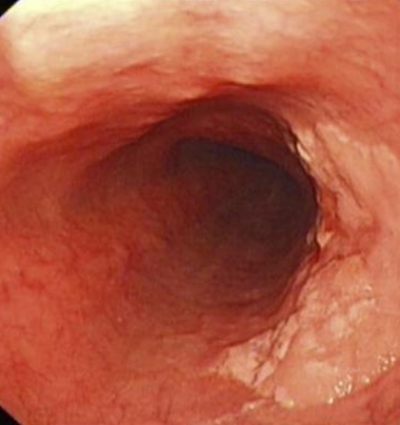

直腸癌圖片

直腸癌晚期症狀 (5)